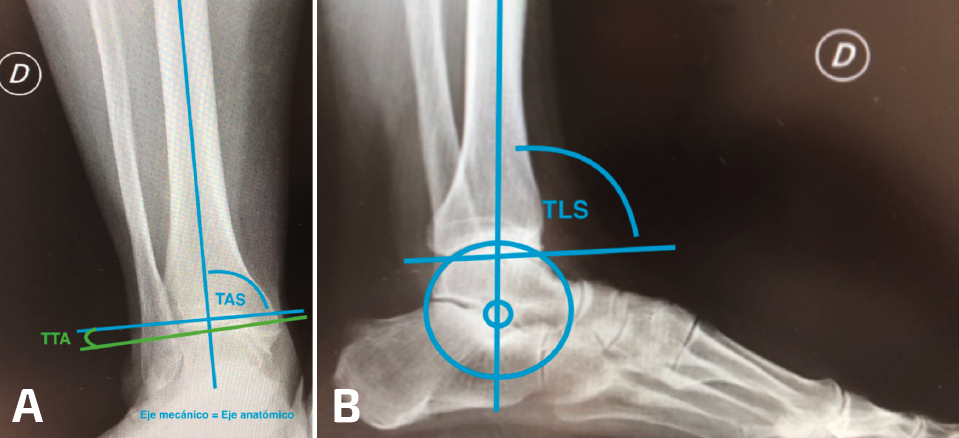

En las radiografías simples con carga se evalúan las deformidades en los planos coronal y sagital. Las mediciones en el plano coronal son la superficie articular tibial distal (TAS-LDTA) con valores normales de 91 a 93° y el ángulo tibiotalar (TTA) con valores normales de 91,5 ± 1,2°. La inclinación talar (talar tilt) se calcula entre la diferencia de la TAS y el TTA. Se considera que un talar tilt con relevancia clínica es aquel mayor de 4°, considerando este valor como límite máximo de normalidad(6,15). La medición en el plano sagital es el ángulo tibial lateral o ángulo tibial anterior distal (TLS-ADTA), con valores normales de 81 ± 5°. En la clasificación de las malalineaciones con OA asimétricas de tobillo se hace más énfasis en la necesidad de corroborar que el centro de rotación del talo (considerado en el centro del proceso lateral del talo) esté en línea con el eje anatómico de la tibia en la radiografía lateral(7,8)(Figura 5).

Figura 5. A: superficie articular tibial (TAS) y ángulo tibiotalar (TTA); B: ángulo tibial lateral (TLS) y centralización de talo en eje anatómico.